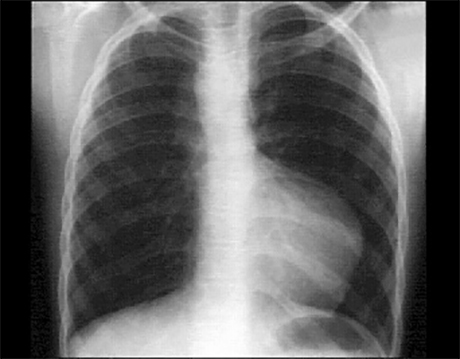

PA

These chest X rays show right ventricular enlargement, a small pulmonary artery trunk and decreased pulmonary vascularity. The PA view suggests right ventricular enlargement by the upturned apex. The small pulmonary trunk is evidenced by the absence of a convex shadow in the left hilar area. Pulmonary vascularity is also diminished, as evidenced by the absence of distal vascular lung markings. These findings are characteristic of Tetralogy of Fallot. Note also the right-sided aortic arch demonstrated by the vascular density along the upper right heart border and the displacement of the trachea to the left. Right-sided aortic arch is seen in about 25% of patients with tetralogy of Fallot.